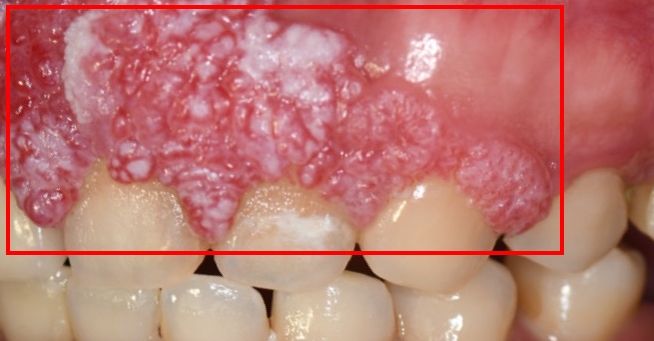

40歲的許小姐於2024年至 中山醫學大學附設醫院(中山附醫)口腔顎面外科就醫,經診斷為上顎牙齦癌,需進行大範圍上顎骨切除手術,不僅影響外觀,口內鄰近腫瘤的10顆牙齒也必須一併拔除,對日後進食與生活功能影響甚鉅。醫療團隊於術前即運用 電腦數位模擬技術,精準規劃腫瘤切除範圍、術後牙齒排列位置,並模擬將植體植入顴骨中,以彌補上顎骨缺損,為後續功能與外觀重建預先做好完整藍圖。

圖:許小姐腫瘤位於上顎齒齦區域

圖:許小姐腫瘤位於上顎齒齦區域手術當日,由中山附醫口腔顎面外科 邱昱瑋、陳怡孜及陳珮吟三位主治醫師組成的醫療團隊主導,採用電腦數位模擬與導航輔助手術。團隊先依模擬結果精準切除腫瘤,再依規劃完成牙齒重建位置,並將植體植入顴骨內,同時結合切割導版與電腦導航系統輔助。所有手術程序於同一日一次完成,包括 上顎口腔癌腫瘤切除、頸部淋巴清除、顴骨植牙與游離皮瓣重建,不僅大幅縮短整體治療時程,也有效降低患者身體與心理負擔。術後,許小姐已成功恢復正常咀嚼功能,生活品質明顯提升。